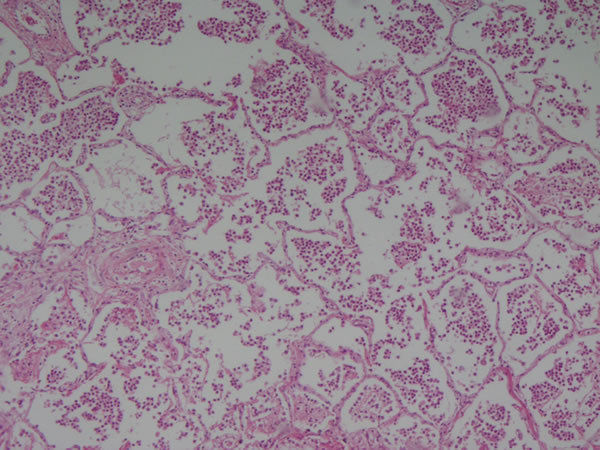

| Pulmão - parênquima pulmonar Edema - edema agudo de pulmão Causas: aumento da permeabilidade vascular | |

Pulmão - parênquima pulmonar Edema - edema agudo de pulmão alvéolos cheios de líquido eosinofílico Causa: aumento da permeabilidade vascular |

Pulmão - parênquima pulmonar Edema - edema agudo de pulmão Achados: Hemorragia intra-alveolar Causa: aumento permeabilidade vascular |

| Pulmão -parênquima pulmonar Edema - edema pulmonar Achados hemorragia, acúmulo de pigmento | |